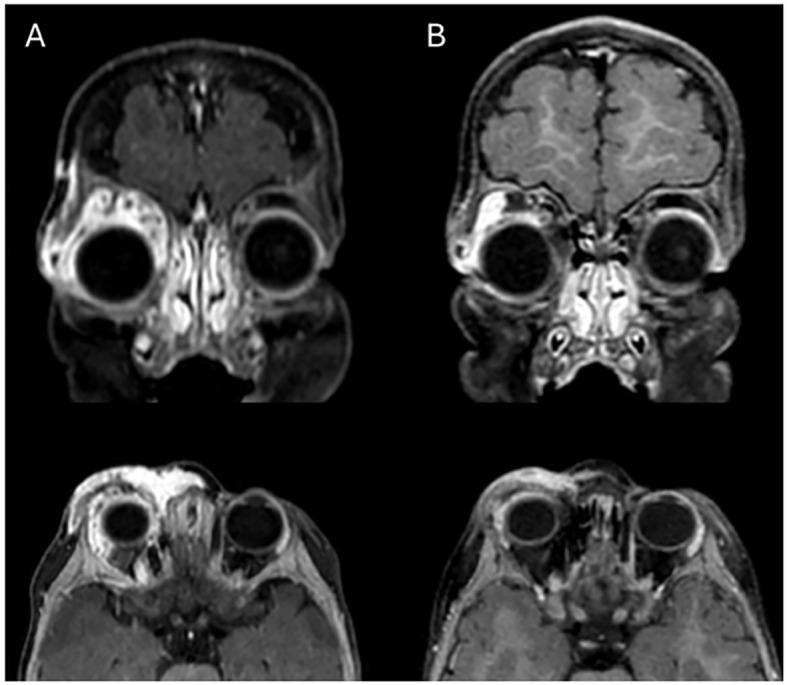

retrospective observational cohort study. Propranolol was administered at an initial oral dose of 1 mg/kg and subsequently increased to 2 mg/kg for 1 year. Outcomes were evaluated by comparing pre- and post-treatment clinical findings, contrast-enhanced ultrasound (CEUS) findings and/or orbital magnetic resonance imaging findings from baseline to 3, 6, 9, 12, 24, and 48 weeks. Regression was graded as follows: satisfactory when 90% and above of the baseline lesion volume and extension decreased, acceptable when 50 to 90%, mediocre when 30 to 50%, poor less than 30%.

回顾性观察队列研究。普萘洛尔初始口服剂量为1mg/kg,随后增至2mg/kg,持续1年。通过比较治疗前和治疗后从基线至3、6、9、12、24和48周的临床检查结果、超声造影(CEUS)结果和/或眼眶磁共振成像结果来评估疗效。消退分级如下:基线病变体积和范围减少90%及以上为满意,减少50%至90%为可接受,减少30%至50%为中等,减少不足30%为差。